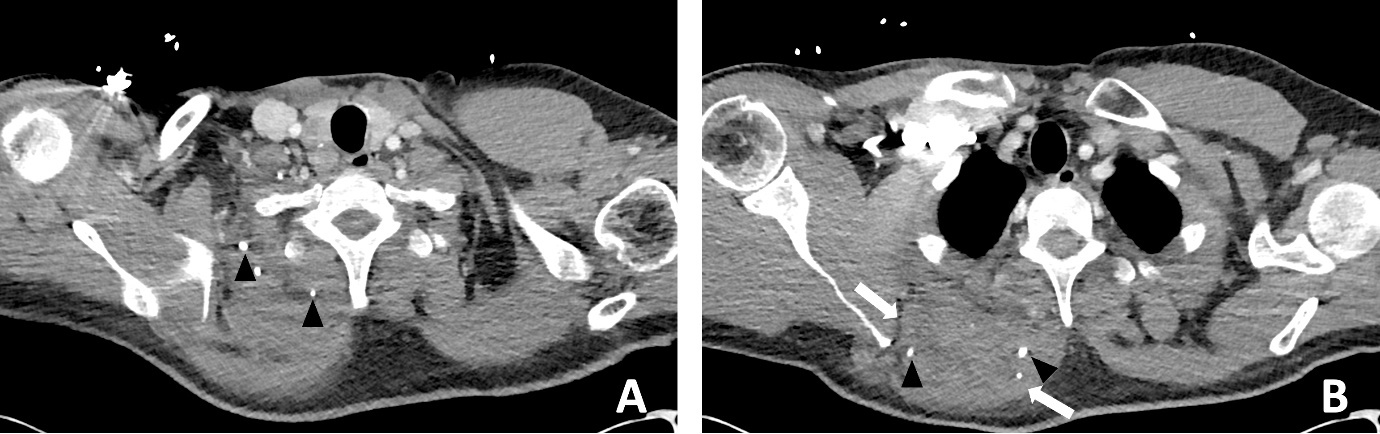

A subsequent washout was performed on day three; intraoperative findings were similar to the first operation. The patient’s fever subsequently settled. An MRI was performed on day 11 to evaluate for possible VM or sarcoma. An MRI revealed a ‘trans-spatial right paraspinal mass involving the trapezius and rhomboid muscles with internal phleboliths, no fluid levels or flow voids, in keeping with a slow flow vascular malformation’ (Figure 4).

In retrospect, the presence of intramuscular phleboliths on CT in the cases presented above was the best clue to the diagnosis of an infected VM. Phleboliths occur in approximately 30 per cent of VMs.15 Intramuscular phleboliths have a limited imaging differential diagnosis and are generally taken to be pathognomic of VM.16 Radiologist and clinician awareness of this rare presentation of VMs is important; if intramuscular phleboliths are identified, the diagnosis of VM should be raised and the use of MRI may further assist in the diagnosis. If clinical doubt remains in an acutely unwell patient, prompt surgery to exclude necrotising soft tissue infection is prudent.

Timely surgical exploration is indicated in septic patients where necrotising soft tissue infection cannot be excluded. However, it is important to consider rare conditions that may present similarly, such as infected VMs. The presence of intramuscular phleboliths on CT, especially in a child, is the best imaging clue to this unusual diagnosis and should not be overlooked.